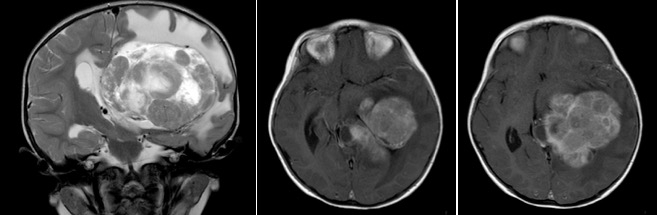

elle se développe le plus souvent dans les ventricules latéraux, rarement dans la fosse postérieure. se développant au sein d’une cavité cérébrale, la tumeur est le plus souvent très volumineuse au moment du diagnostic (cf. ci-dessous).

elle atteint souvent le jeune enfant, voire le nourrisson (médiane de l’âge 26,5 mois), plus souvent le garçon (M/F ratio 1,67) et à gauche (ratio G/Dt 4,5) ; elle peut survenir dans le cadre d’un syndrome de prédisposition tumorale (syndrome de Li-Fraumeni par mutation p53).